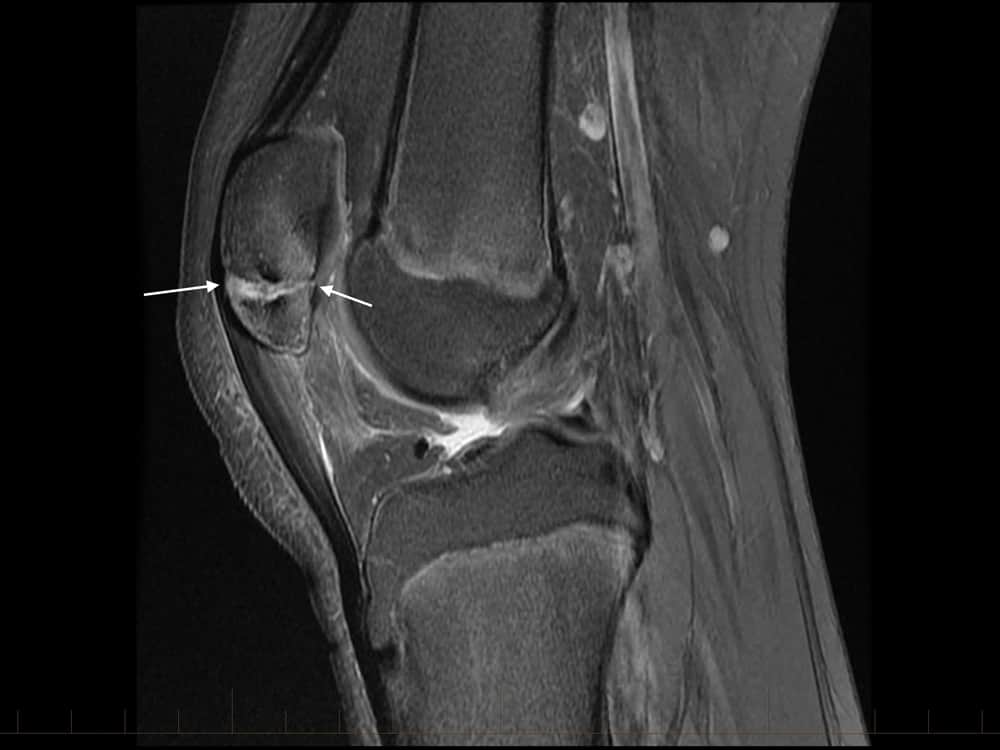

Xương bánh chè 2 mảnh

» Thông tin: Nam giới – 14 tuổi.

» Lâm sàng: Đau khớp gối.